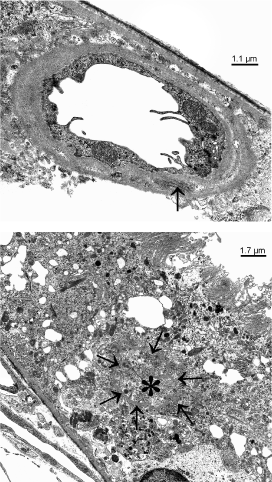

If conglomerates of capillaries were studied within the RPE layer, the endothelium always showed fenestrations. Sections of single vessels, in contrast, also showed preserved non-fenestrated endothelium (Figure 4A). At places, remnants of former retinal vessels named ‘ghost vessels’ were seen within the RPE (Figure 4B).

Figure 4 A, B. Transmission electron micrographs of a 6 months old dystrophic RCS rat showing newly formed vessels within the RPE layer.) single vessels show a non-fenestrated endothelium with microvilli-like processes and long spacin collagen (arrow). b) ‘ghost vessels’ within the RPE show a continuous basal membrane (arrows), filled with collagen (asterisks), but no endothelium and no lumen.